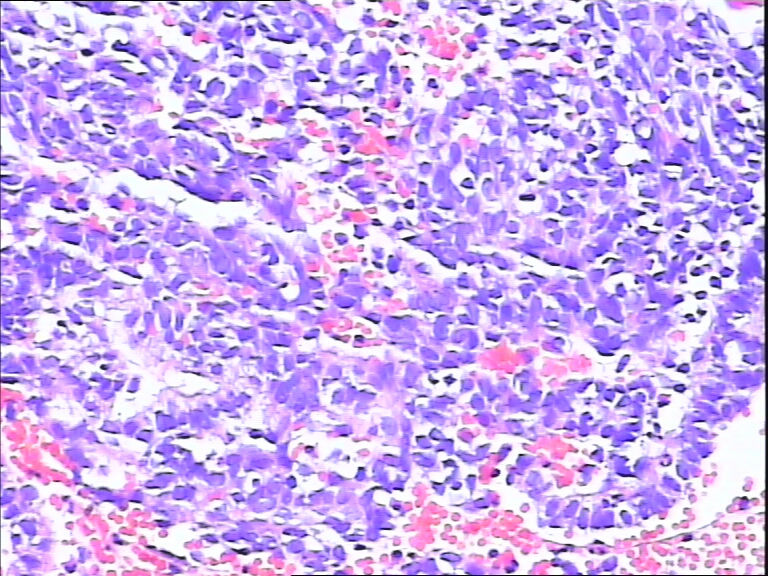

41岁,停经5年再出血。

• 宫内膜图3

图3

流血期子宫内膜,腺体反应不同步

腺体反应不同步,部分增生期改变,部分上皮细胞有核下空泡呈早分泌期改变,是用过药物?

片子不是很清楚,像是月经期子宫内膜

流血期子宫内膜,腺体反应不同步。

腺体增生,部分腺上皮有分泌。